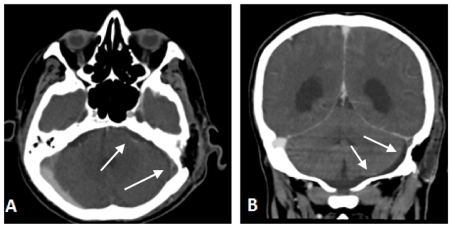

The intracranial or cerebral venous system is a network of nerves made up of two systems working together the superficial system and the deep system(1) The superficial cerebral system has sagittal sinuses and cortical veins The sinuses and the veins both drain deoxygenated blood from the surfaces of the brain's hemispheres(2)Dural venous sinus thrombosis is diagnosed on CT venography and MRV but CT plain brain is the initial radiological investigation Most of the time CT shows signs such as hyper density, hyperdense delta sign On this scan a subtle linear hyperdensity was seen in the region of right transverse sinus and confluence of sinusesApr 12, 13 · Variations in intracranial dural venous sinus anatomy have been widely reported in humans, but there have been no studies reporting this in dogs The purpose of this retrospective study was to describe variations in magnetic resonance (MR) venographic anatomy of the dorsal dural venous sinus system in a sample population of dogs with

Venous sinus anatomy appeared unusual, and thus magnetic resonance venography was performed, which identified the OS as the main drainage pathway for the entire brain, providing the sole drainage between the superior sagittal sinus and the jugular veins through the marginal sinus Both the transverse and sigmoid sinuses were hypoplastic, andThe dural venous sinuses (also called dural sinuses, cerebral sinuses, or cranial sinuses) are venous channels found between the endosteal and meningeal layers of dura mater in the brainBACKGROUND AND PURPOSE Patients with intracranial hypotension (IH) demonstrate intracranial venous enlargement with a characteristic change in contour of the transverse sinus seen on routine T1weighted sagittal imaging In IH, the inferior margin of the midportion of the dominant transverse sinus acquires a distended convex appearance;